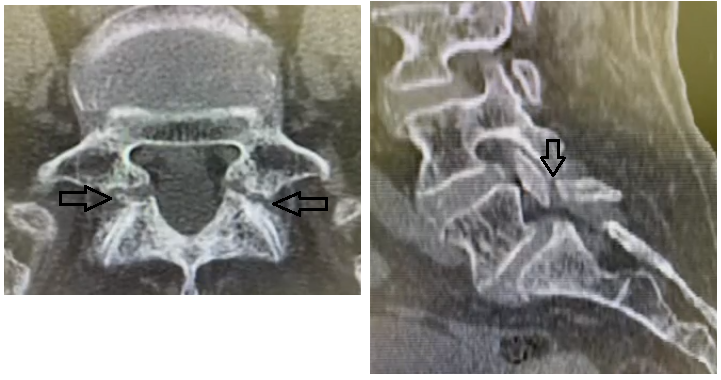

• Na avaliação radiológica, qual a utilidade da tomografia na espondilolistese ístimica?

A

• Proporciona um melhor delineamento do defeito